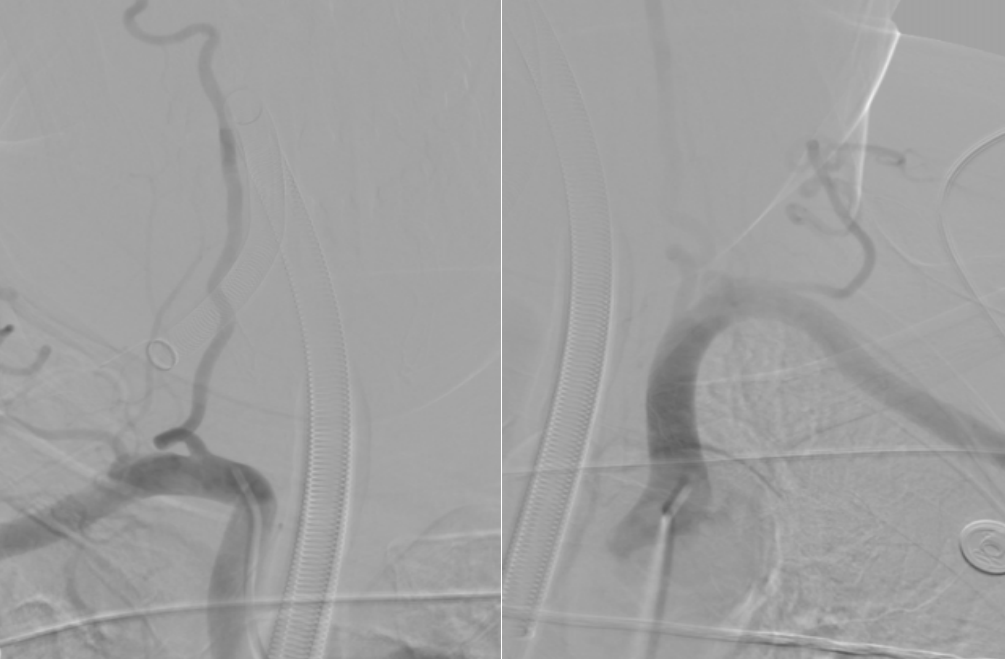

DSA示:基底动脉下段闭塞。

300cm Synchro微导丝

SacSpeed®2.0mm×15mm球囊

Neuroform EZ支架 4mm✕20mm